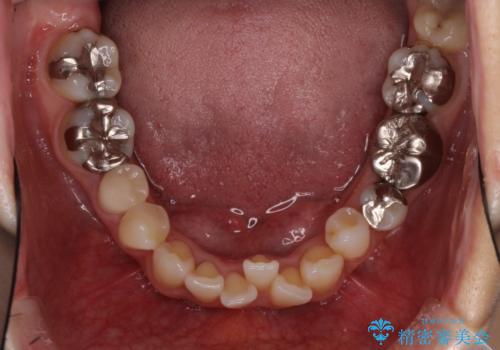

上下の骨幅を改善したことで、スムーズに歯列矯正を行うことができました。

矯正治療中に近医で銀歯を外す治療を開始したため、治療後に奥歯の咬み合わせが不十分ですが(こちらは近医での治療により改善するとのこと)、歯列と咬み合わせが改善され、患者様には大変満足していただきました。